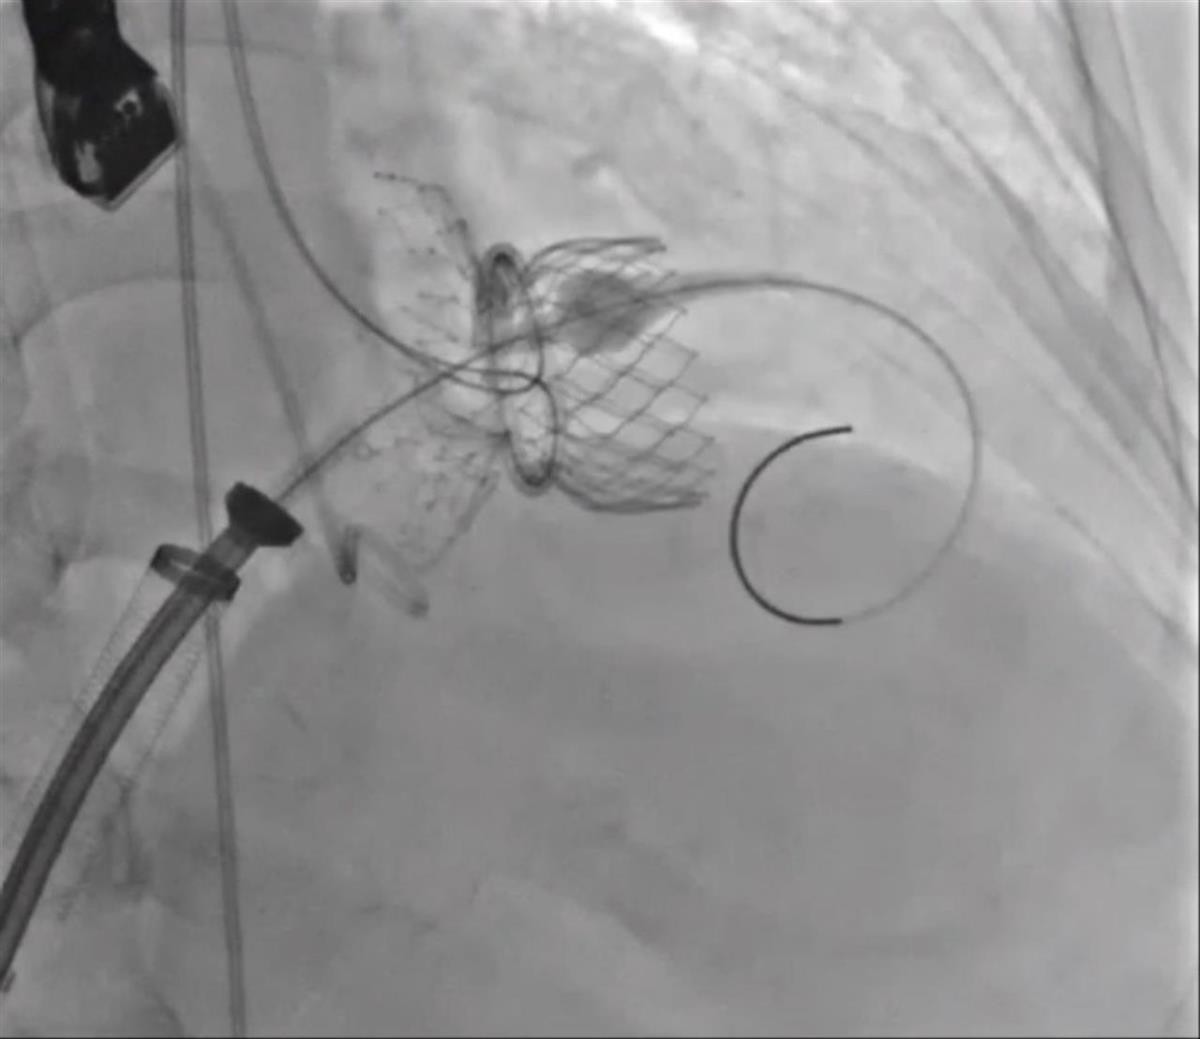

近期,心血管医院医师团队为胡奶奶实施经导管二尖瓣置换术。手术通过患者桡动脉建立主动脉根部监测,经左股动脉路径行二尖瓣闭合成环,经右股静脉行房间隔穿刺建立瓣膜输送轨道,在造影及三维超声融合引导下完成人工瓣膜精准锚定与释放。

经导管二尖瓣置换术术中